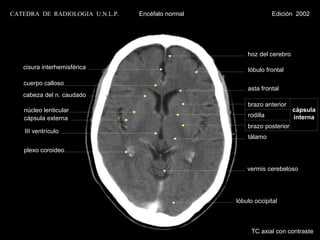

hoz del cerebro

cisura interhemisférica                             lóbulo frontal

cuerpo calloso

asta frontal

cabeza del n. caudado

brazo anterior

núcleo lenticular                                                     cápsula

cápsula externa                                     rodilla           interna

brazo posterior

III ventrículo

tálamo

plexo coroideo

vermis cerebeloso

lóbulo occipital

TC axial con contraste